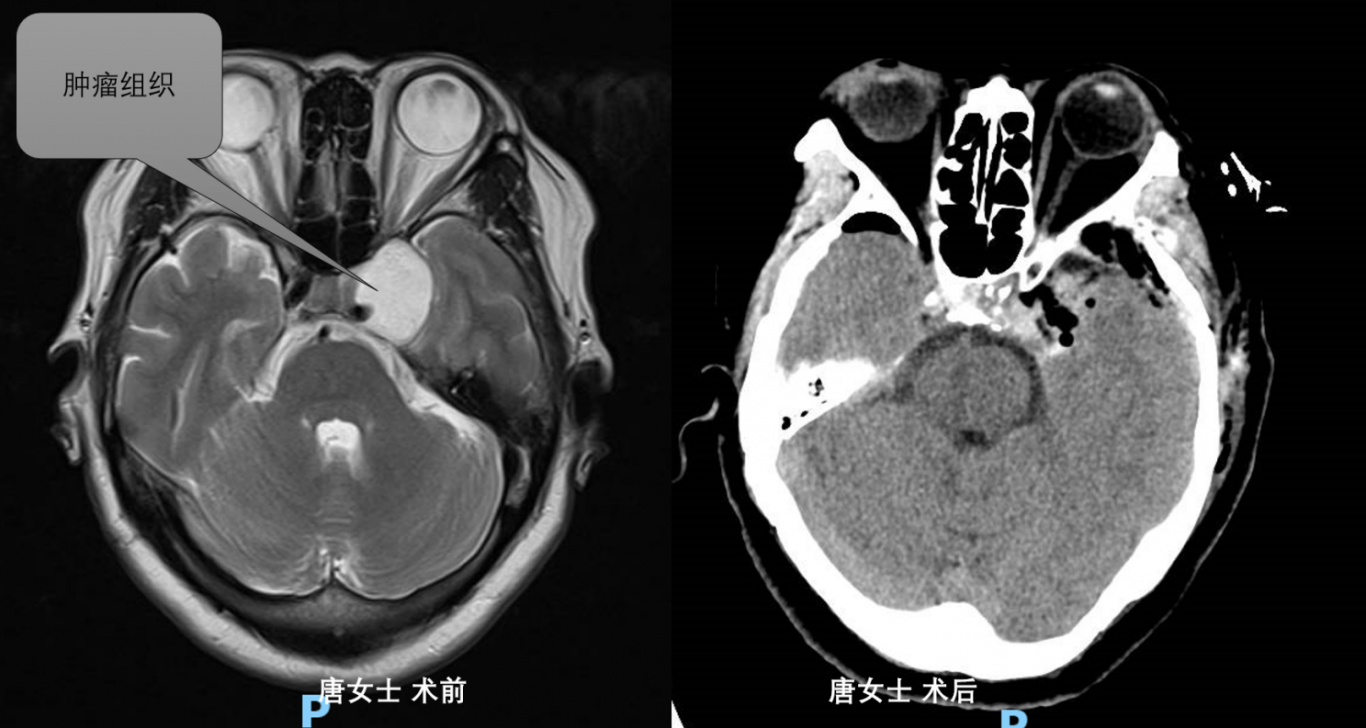

案例三:

龙马潭区唐女士因左眼视物不清,入院后检查提示鞍区占位。术后病检提示海绵状血管瘤。